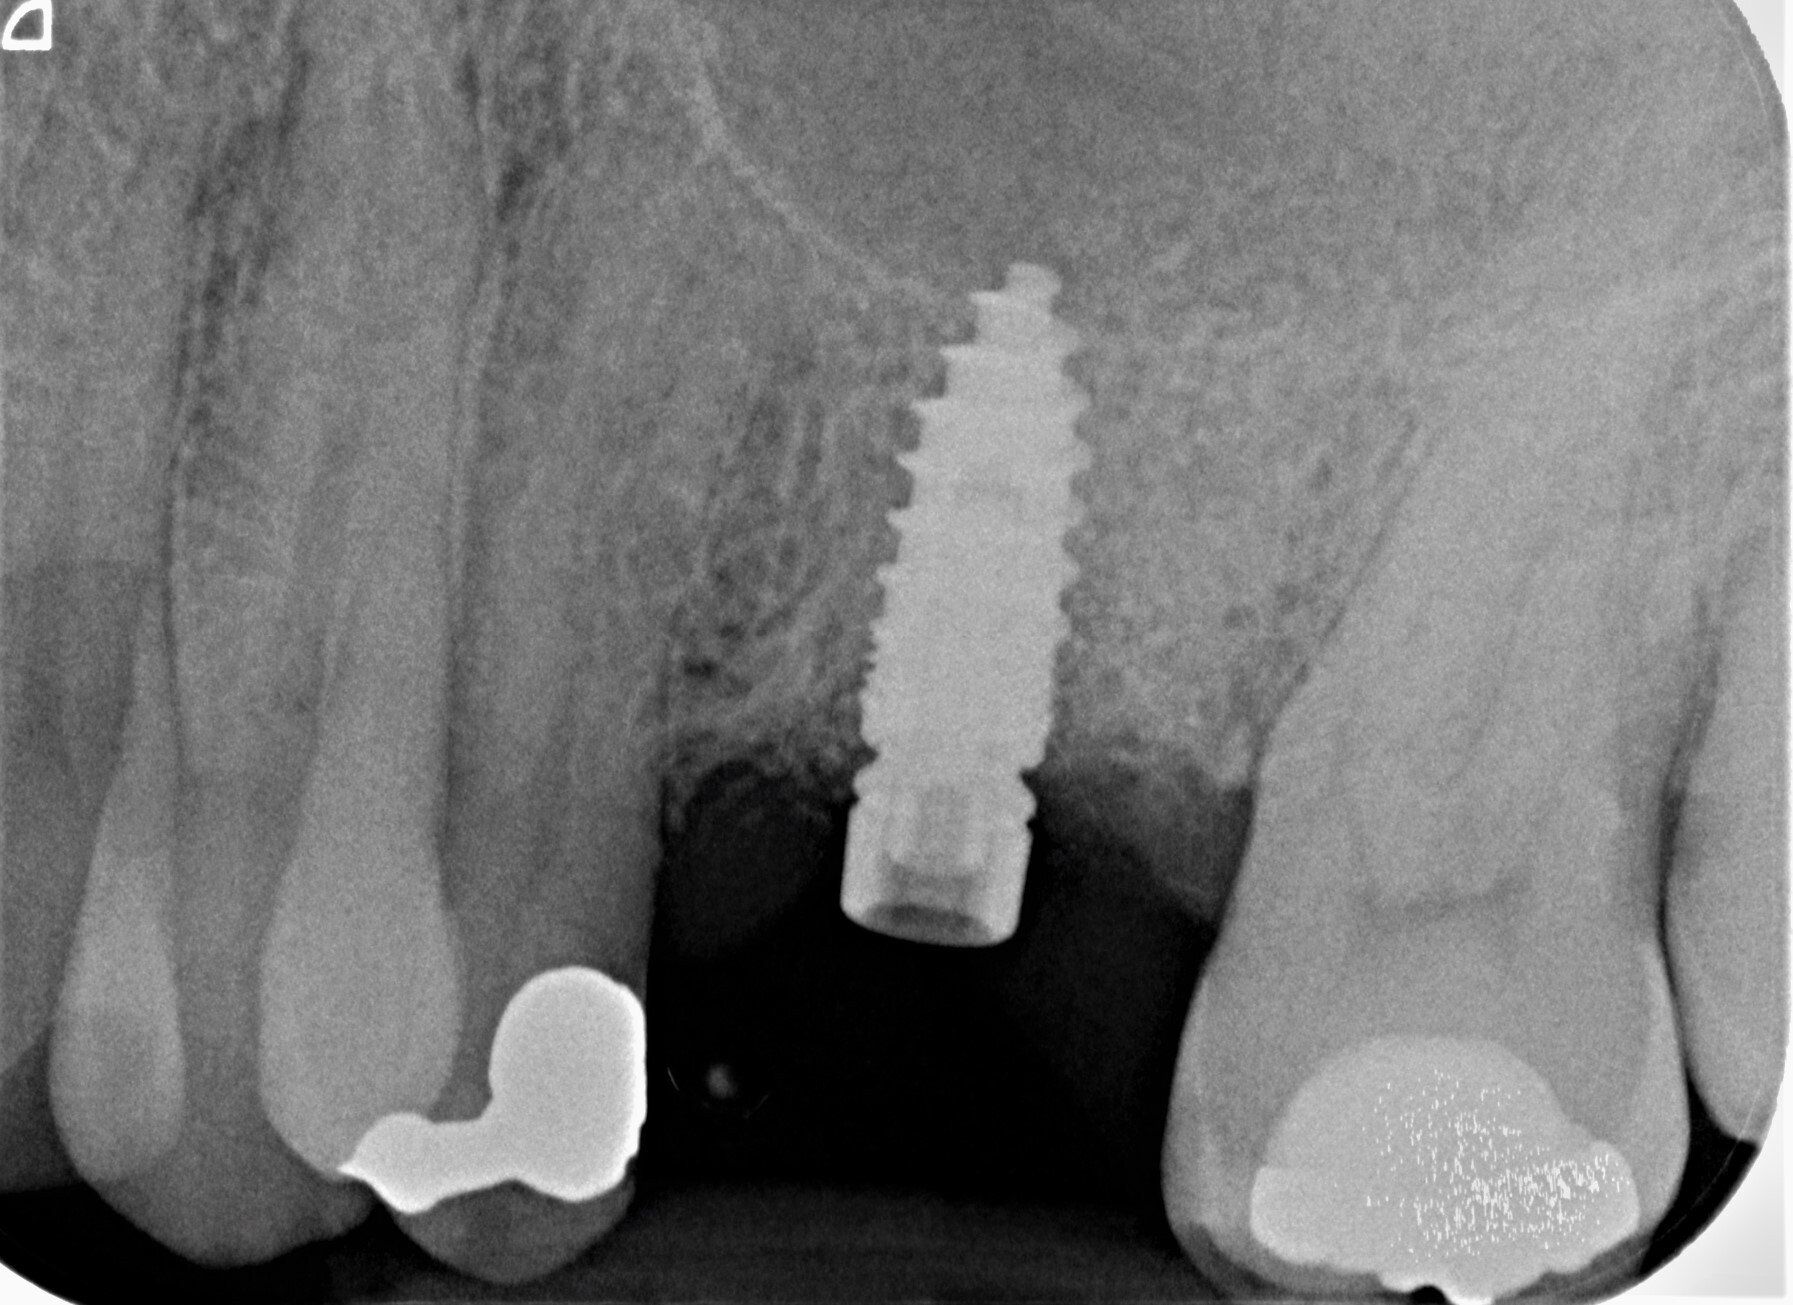

Durch den Verlust des Zahnes wandelt sich der Kieferknochen um. Nach der oberflächlichen Heilung wird das knöcherne Zahnfach vom Körper rasch abgebaut. Knochen ist für den Körper ein "teures" Gewebe, und ohne die funktionelle Kaubelastung durch einen Zahn gibt es für den Körper keinen Grund mehr, das knöcherne Zahnfach zu erhalten. Allein im ersten Jahr nach der Zahnentfernung gehen 50% des umgebenden Knochens verloren! Das ist insbesondere dann von Nachteil, wenn geplant ist, später ein Implantat für den Ersatz des Zahnes zu setzen. Ohne kiefererhaltende Maßnahmen reicht oftmals der nach der Heilung verbliebene Knochen nicht mehr aus, ein hinreichend großes Implantat einzusetzen bzw. dieses auch ideal zu positionieren.

Aus diesem Grund war jahrelang der Goldstandard zum Ersatz von Knochen - körpereigener Knochen! Dieser musste in verschiedenen Spenderregionen "gewonnen" werden, was für den Patienten oftmals eine weitere Operation bedeutete. Allerdings war schon länger bekannt, dass das Zahnbein (Dentin) eine fast identische Mineralzusammensetzung und die gleichen Eiweißstoffe wie Knochen besitzt.

Das Verfahren ist schonend und erfordert keinen zweiten Eingriff. Materialien tierischen Ursprungs werden vermieden. Die Aufbereitung findet direkt nach der Zahnentfernung in unserem Labor statt. Nach ca. 25 Minuten kann das Knochenfach aufgefüllt werden. Der Bereich muss für zwei Wochen geschont und auf der anderen Seite gekaut werden. Es sollte zwei Tage nicht geraucht werden. Alles weitere können wir den Selbstheilungskräften unsres Körpers überlassen.